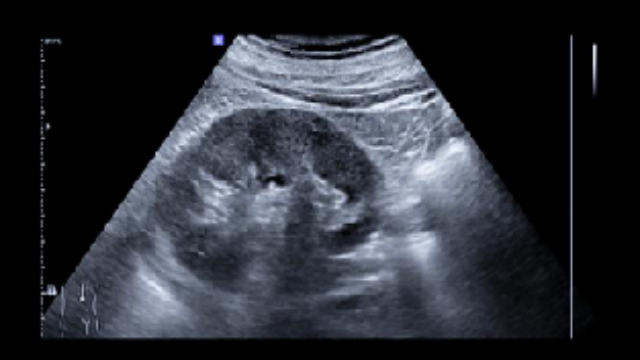

肝膽結(jié)石的臨床管理遵循個(gè)體化分層原則,結(jié)合結(jié)石特性與患者整體狀態(tài)提供適宜方案。對(duì)于無(wú)癥狀或體積較小的膽固醇類(lèi)結(jié)石,口服藥物如熊去氧膽酸可調(diào)節(jié)膽汁成分,逐步促進(jìn)結(jié)石溶解,減少侵入性操作需求。中西醫(yī)協(xié)同策略進(jìn)一步擴(kuò)展了保守路徑,例如中藥復(fù)方通過(guò)疏肝利膽、調(diào)節(jié)代謝環(huán)境輔助排石,為特定體質(zhì)患者提供補(bǔ)充選擇。當(dāng)結(jié)石引發(fā)膽管梗阻或炎癥時(shí),內(nèi)鏡技術(shù)(如ERCP)經(jīng)自然腔道直接取石或碎石,對(duì)膽總管下端嵌頓性結(jié)石尤為適用,避免開(kāi)放手術(shù)創(chuàng)傷。針對(duì)肝內(nèi)多發(fā)結(jié)石或合并膽管狹窄的復(fù)雜病例,腹腔鏡聯(lián)合膽道鏡實(shí)現(xiàn)同步解決結(jié)石與修復(fù)狹窄,微小切口設(shè)計(jì)縮短術(shù)后恢復(fù)時(shí)間;若合并局限性肝萎縮,肝切除術(shù)可阻斷病變進(jìn)展并移除病灶512。高齡或體質(zhì)虛弱者通過(guò)多學(xué)科協(xié)作(如影像引導(dǎo)結(jié)合麻醉優(yōu)化)提升操作安性。身體不適感少,術(shù)后感受良好。安徽如何選結(jié)石臨床解決方案供應(yīng)

整合多種技術(shù)手段,形成互補(bǔ)協(xié)同的診療體系,根據(jù)患者結(jié)石位置、數(shù)量及個(gè)體差異靈活定制干預(yù)路徑。對(duì)于肝內(nèi)膽管結(jié)石,可結(jié)合腹腔鏡肝部分切除與術(shù)中膽道鏡取石,在移除病灶的同時(shí)保留健康肝組織,降術(shù)后膽管狹窄風(fēng)險(xiǎn);膽總管結(jié)石則常采用ERCP(經(jīng)內(nèi)鏡逆行胰膽管造影)聯(lián)合十二指腸切開(kāi)術(shù),通過(guò)自然腔道實(shí)現(xiàn)無(wú)創(chuàng)取石,避免開(kāi)腹手術(shù)的創(chuàng)傷。若遇復(fù)雜病例(如合并膽管狹窄或先天性膽管囊腫),可同步實(shí)施腹腔鏡膽腸吻合術(shù),重建膽汁引流通道,從根源解決梗阻難點(diǎn)。江蘇發(fā)展結(jié)石臨床解決方案廠家并發(fā)癥控制良好,操作過(guò)程平穩(wěn)順利。

肝膽結(jié)石臨床解決方案的優(yōu)勢(shì)在于整合多種技術(shù)手段,形成互補(bǔ)協(xié)同的診療體系,根據(jù)患者結(jié)石位置、數(shù)量及個(gè)體差異靈活定制干預(yù)路徑。對(duì)于肝內(nèi)膽管結(jié)石,可結(jié)合腹腔鏡肝部分切除與術(shù)中膽道鏡取石,在移除病灶的同時(shí)保留健康肝組織,降術(shù)后膽管狹窄風(fēng)險(xiǎn);膽總管結(jié)石則常采用ERCP(經(jīng)內(nèi)鏡逆行胰膽管造影)聯(lián)合十二指腸切開(kāi)術(shù),通過(guò)自然腔道實(shí)現(xiàn)無(wú)創(chuàng)取石,避免開(kāi)腹手術(shù)的創(chuàng)傷。若遇復(fù)雜病例(如合并膽管狹窄或先天性膽管囊腫),可同步實(shí)施腹腔鏡膽腸吻合術(shù),重建膽汁引流通道,從根源解決梗阻難點(diǎn)。高齡或基礎(chǔ)難點(diǎn)患者則優(yōu)先選擇體外沖擊波碎石(ESWL)等非侵入性操作,通過(guò)能量傳導(dǎo)逐步粉碎結(jié)石,配合利膽藥物促進(jìn)碎片排出。安徽如何選結(jié)石臨床解決方案供應(yīng)